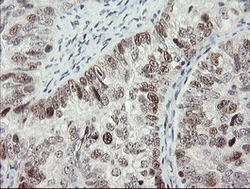

Immunohistochemistry

LS-C175219 IHC